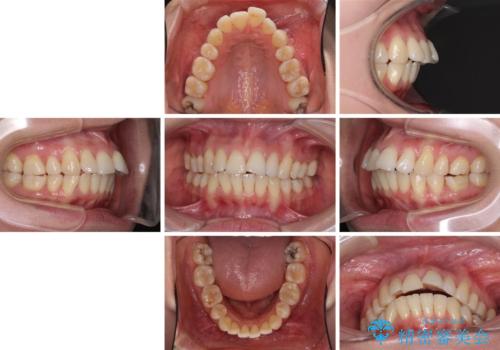

- 上の前歯の出っ歯を治したいとのことで来院された患者様です。

後戻りによる再矯正というもともあり、インビザラインを希望されていました。

上顎の歯は後方移動とIPR(歯と歯の間を削る)によって口元が引っ込むように、下顎は歯列全体の拡大とIPRによって上顎とバランスよく咬み合うように設計し、インビザラインにより治療を行うこととしました。

治療を開始して暫くして、勤務先から2年以上帰国することができず、それまでの移動がほとんど後戻りしてしまい、帰国後に再度後戻りをリカバリーするための治療を行うこととなりました。

5年以上の治療期間がかかりましたが、気になっている部分を改善することができました。